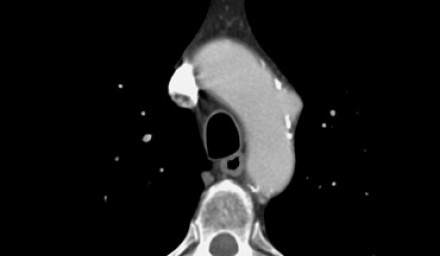

- Гемиперикард, гемомедиастенум и гемиторакс являются грозными осложнениями диссекции аорты.

- Ниже представлен пациент с полным тромбированием ложного просвета. Спустя 5 дней после первого обращения пациент жалуется на резкую боль в груди, а снимках визуализируется кровоток в ложном просвете.

- Увы, но пациентка не могла продолжить лечение хирургически по разным причинам, поэтому лечилась медикаментозно.

![18]()

Гемиперикард, гемиторакс, гемомедиастенум

![19]()

![20]()